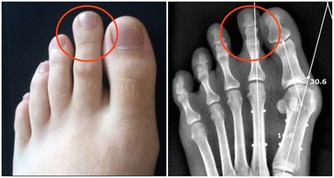

運動可以使我們的身體變得更加健康,這是我們都知道的事情。實際上,運動也有利於幫助我們的身體趕走濕氣。在我們進行體育鍛煉的時候,身體的各個機能就會被充分調動起來,新陳代謝會加快,血液循環系統功能會提高,血液循環會加快,身體內的濕氣也會被排除一部分。因此,想要趕走濕氣,進行運動是必不可少的,平時多做一些有氧運動,或者飯後散散步,這些都可以幫助我們趕走身體的濕氣。